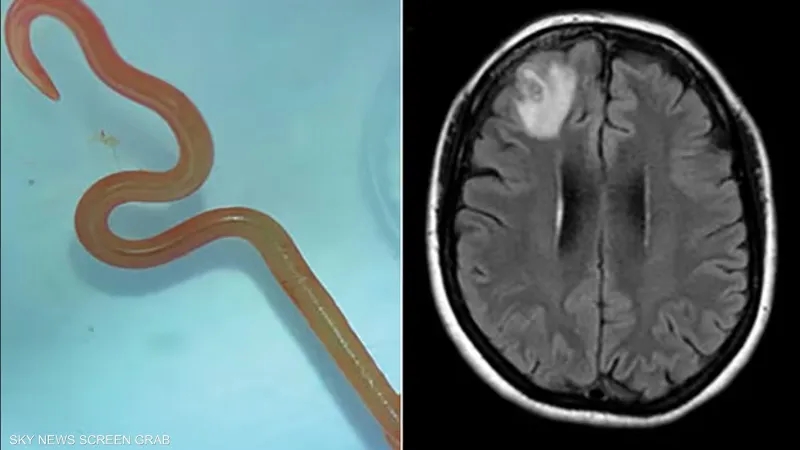

أخبار البلد -   نجح فريق طبي في الصين مؤخراً في إنقاذ حياة رجل بعدما أزالوا دودة ملتوية حية بطول 18 سنتيمتراً من دماغه، كانت قد استقرت هناك لسنوات نتيجة تناوله أجزاء نيئة من ثعبان.

غير أن حالته ساءت بشكل مفاجئ الشهر الماضي، ما استدعى تدخلاً جراحياً عاجلًا. وخلال عملية معقدة لفتح الجمجمة، تمكن الأطباء من استخراج دودة شريطية بيضاء طويلة كانت تتلوى داخل دماغه.

وبحسب الأطباء، تعود إصابة المريض إلى حادثة وقعت قبل سنوات، حين ابتلع مرارة ثعبان نيئة كتحدٍّ، دون أن يدرك أن اليرقات الطفيلية المعروفة باسم سبارغانوم قد دخلت جسمه عبر هذا التصرف. وبمرور الوقت، شقت اليرقات طريقها حتى استقرت داخل دماغه.

ويُعرف هذا الطفيل باسم داء السبارغانوزيس، وهو عدوى تسببها يرقات الدودة الشريطية التي تعيش عادة في الضفادع والثعابين والطيور. وينتقل المرض إلى الإنسان عند تناول لحوم هذه الحيوانات نيئة أو غير مطهوة جيداً، وقد يؤدي إلى أعراض عصبية خطيرة، بل الموت في بعض الحالات.